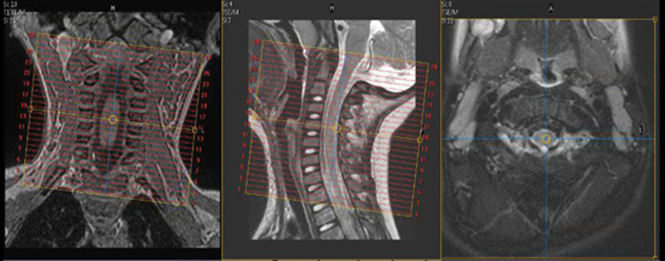

| Plane | Weighting | Mode | Slice | Gap | FAT SAT | FOV | Notes |

|---|---|---|---|---|---|---|---|

| SAG | T2 | TSE | 2.5mm | 0.5mm | None | 20cm | Include Facet Joints |

| SAG | T1 | TSE | 2.5mm | 0.5mm | None | 20cm | Include Facet Joints |

| SAG | STIR | TSE | 2.5mm | 0.5mm | None | 20cm | Include Facet Joints |

| SAG | T2 FFE | GRE | 2.5mm | 0.5mm | None | 20cm | Include Facet Joints |

| AX | T2 | TSE | 2.5mm | 0.5mm | SPAIR | 20cm | Include Facet Joints |

| AX | T1 | TSE | 2.5mm | 0.5mm | None | 20cm | Include Facet Joints |

| COR | T2 | TSE | 2.5mm | 0.5mm | SPIR | 20cm | Include Facet Joints |